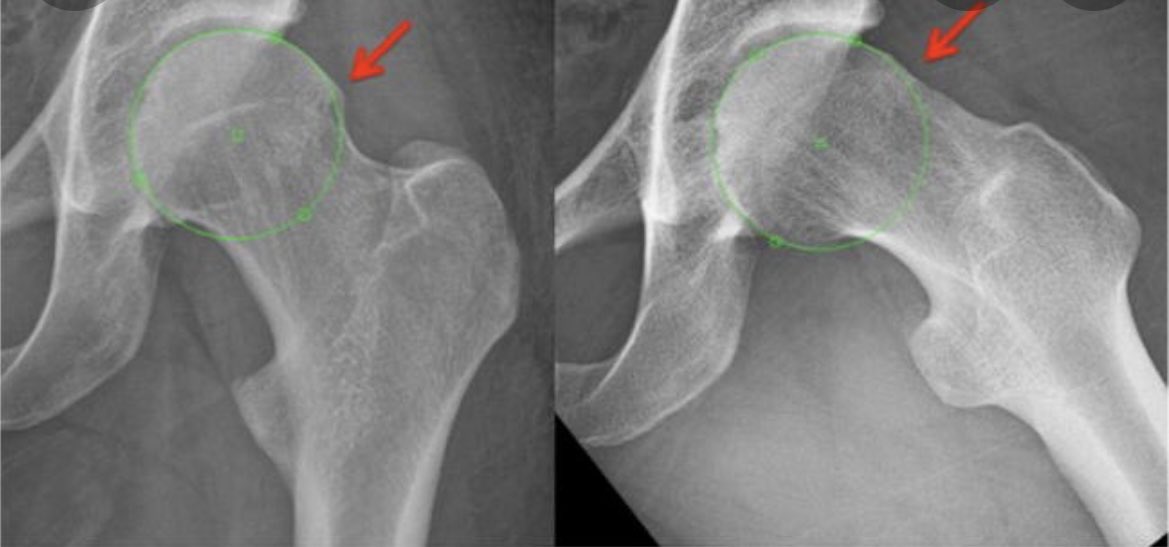

3) CAM Morphology - 3:1 prevalence in males (Kuhn et al 2015). Osteophytosis of the femoral head/neck due. These can occur primary (physiological response to loading) OR secondary (pre-existing hip pathology). XR for A-angle, >50-55 is considered CAM. Image